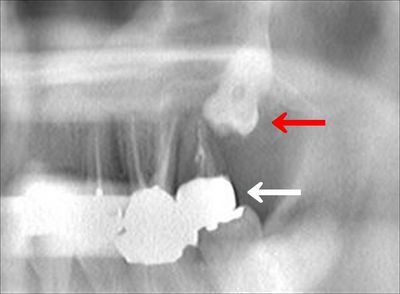

パノラマX線画像による左上大臼歯部分のレントゲンです。

左上第二大臼歯(白矢印)が重度の歯周病に侵され、骨への稙立が失われています。

その奥には親知らずが完全に埋伏しています。(赤矢印)